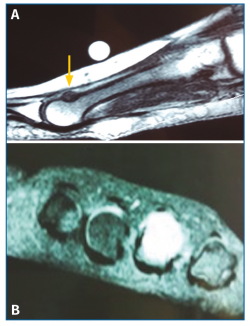

Se solicitó una resonancia magnética (RM) en dispositivo convencional de 1,5 T que no objetivó patología neurológica intermetatarsiana, pero en la que se observaba una alteración de señal localizada en la diáfisis-epífisis distal del cuarto metatarsiano, hipointensa en T1 e hiperintensa en T2, compatible con edema óseo, y que se informó como fractura de estrés (Figura 2).

Figura 2. Resonancia magnética en corte coronal (A) y axial (B) que muestra una alteración de señal hiperintensa en T2 a nivel diáfisis-epífisis del 4.º metatarsiano.